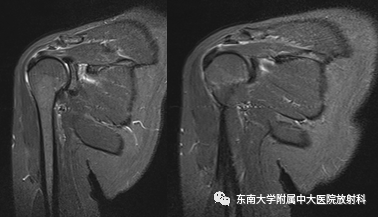

肩峰下撞击综合征影像表现